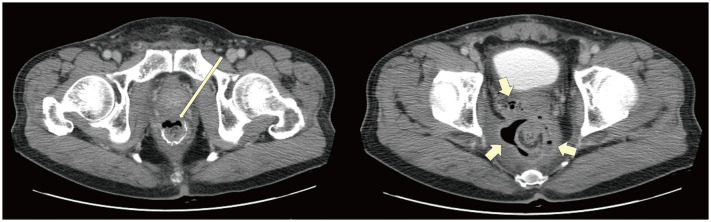

The anticancer drugs have evolved significantly, spanning molecular targeted therapeutics (MTTs), immune checkpoint inhibitors (ICIs), chimeric antigen receptor T-cell (CAR-T) therapy, and antibody-drug conjugates (ADCs). Complications associated with these drugs vary widely based on their mechanisms of action. MTTs that target angiogenesis can often lead to complications related to ischemia or endothelial damage across various organs, whereas non-anti-angiogenic MTTs present unique complications derived from their specific pharmacological actions. ICIs are predominantly associated with immune-related adverse events, such as pneumonitis, colitis, hepatitis, thyroid disorders, hypophysitis, and sarcoid-like reactions. CAR-T therapy causes unique and severe complications including cytokine release syndrome and immune effector cell-associated neurotoxicity syndrome. ADCs tend to cause complications associated with cytotoxic payloads. A comprehensive understanding of these drug-specific toxicities, particularly using medical imaging, is essential for providing optimal patient care. Based on this knowledge, radiologists can play a pivotal role in multidisciplinary teams. Therefore, radiologists must stay up-to-date on the imaging characteristics of these complications and the mechanisms underlying novel anticancer drugs.

Abstract Image